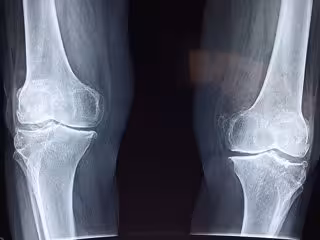

Así, las manifestaciones de esta patología en los pacientes pediátricos son múltiples, tal y como explica la experta. Pueden presentar anomalías a nivel craneal y, además, son niños propensos a padecer problemas dentales; enfermedad esquelética, que determina deformidades en las extremidades inferiores, y retraso en el crecimiento; disminución de la fuerza muscular en las piernas; y dolor óseo y articular, sobre todo en la rodilla, parte superior de la pierna y el tobillo.

"Al producirse un crecimiento anómalo de los huesos con especial afectación de las extremidades inferiores, con arqueamiento por el raquitismo, esto da lugar a dificultades motoras", ha concretado la pediatra.